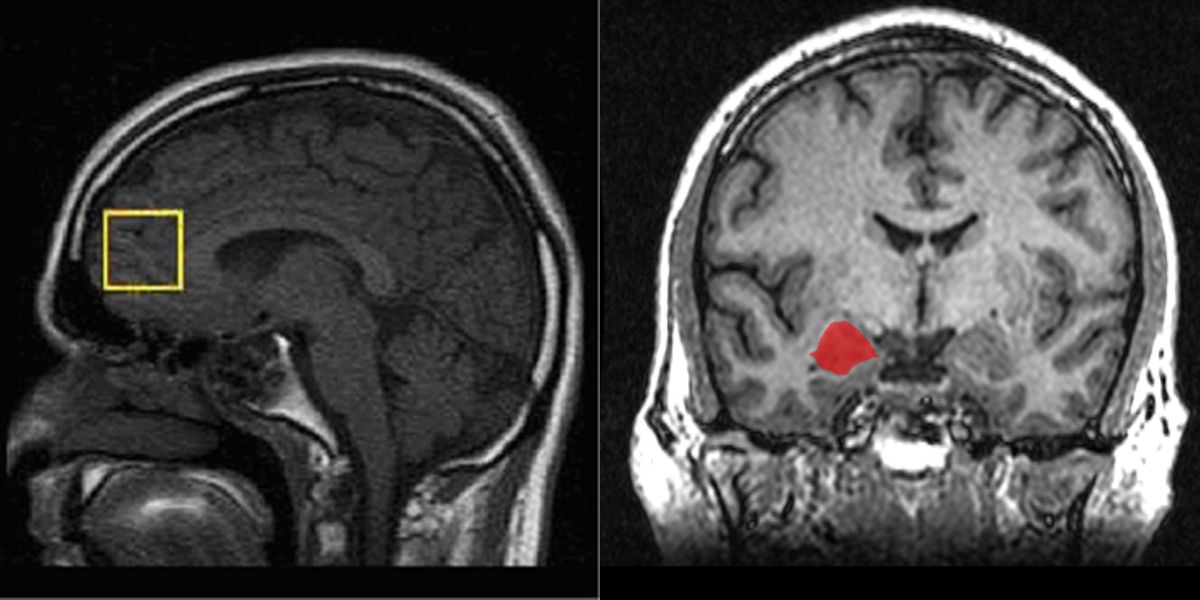

ซ้าย- Medial Prefrontal Cortex ขวา – Amygdala

แต่ในกรณีผู้สูงอายุ พวกเขาจะเชื่อมโยงกับความรู้สึกเชิงบวกง่าย ไม่ชอบการถูกเร่งเร้า ซึ่งในปี 2013 ทีมวิจัยจากมหาวิทยาลัย Southern California พบว่าสมองของผู้สูงอายุจะมีปฏิกิริยาตอบสนองต่อถ้อยคำที่มีความหมายดี เมื่อทำการตรวจกิจกรรมสมองด้วยเทคนิค fMRI พบบริเวณสมองส่วน Medial Prefrontal Cortex และ Amygdala มีหน้าที่ควบคุมการตัดสินใจและอารมณ์จะตอบสนองสูงกว่าคนวัยอื่นๆ ทำให้คนสูงอายุมีแนวโน้มช่างเห็นใจ ปรารถนาดี และอยากแชร์อะไรดีๆ ต่อไปให้คุณ